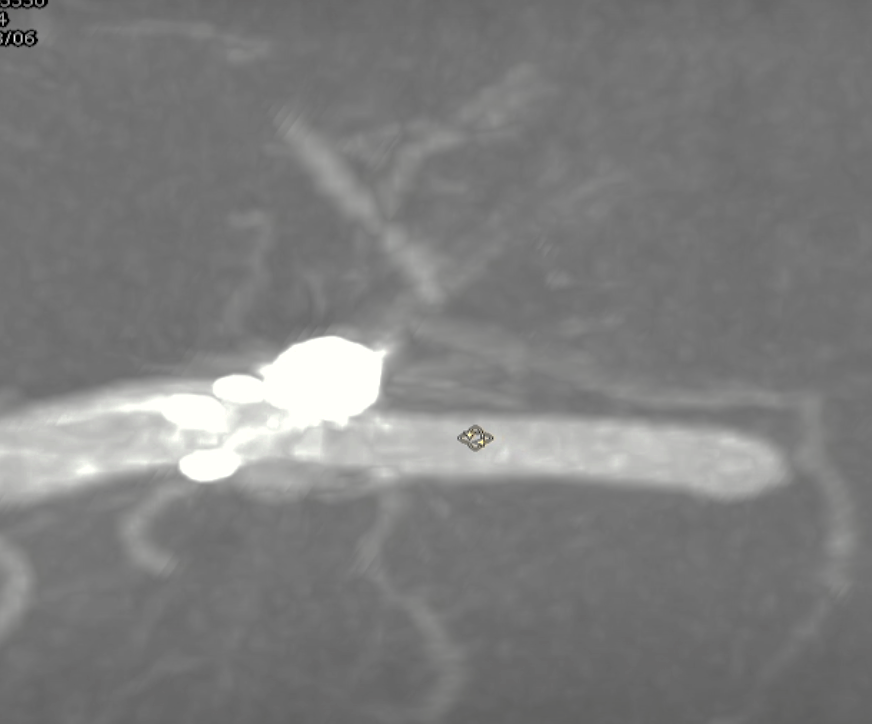

术后支架重建:支架打开良好,近端Marker位于颈内动脉分叉处

术后Vaso CT未见出血,患者神清语利,神经系统查体阴性。